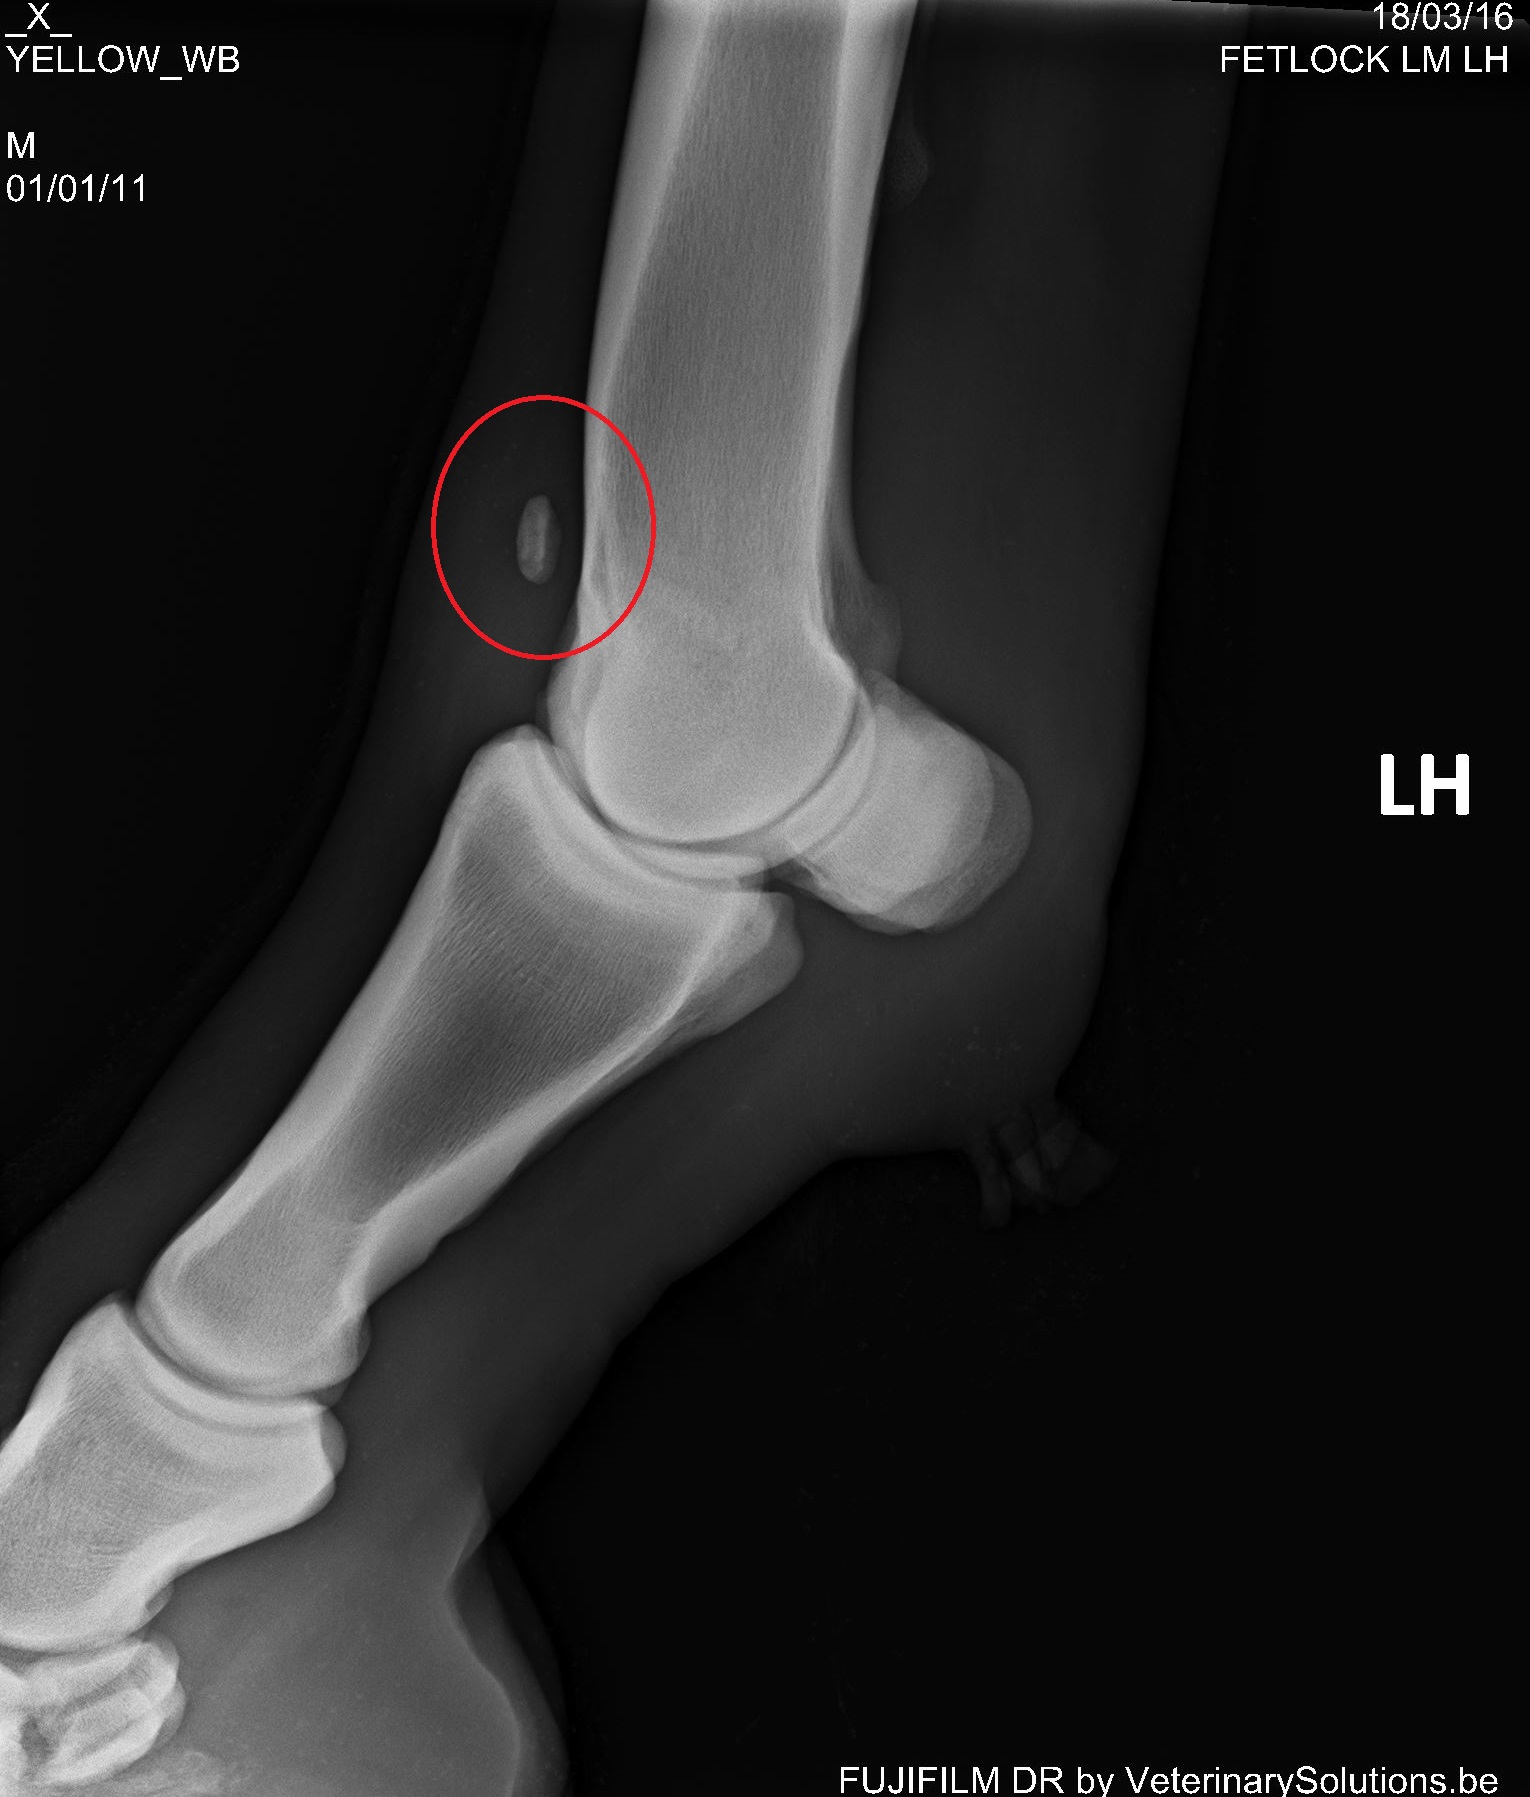

临床兽医可以通过临床症状作出初步诊断。确诊需要做X线片检查。例如上图中红圈内是一块很明显的游离于球节的骨软骨碎片。可以采用关节镜做进一步检查,以确定关节的损伤程度并通过微创手术去除软骨碎片,如下图。在国外,马主通常会在马匹三四岁的时候请兽医做一次全面的X线片检查评估它们的关节,一旦发现OCD,及早进行手术能最大程度减少其对关节的损伤,保住马儿未来的运动生涯。